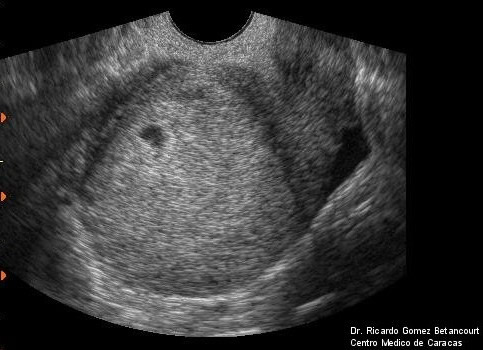

Pues efectivamente hoy hemos tenido el primer susto. Las temidas pérdidas han llegado. Evidentemente nos hemos dado un susto de muerte porque eso es lo último que esperas cuando estás embarazada. Ha sido muy abundante y rojo intenso, como si me hubiera venido la regla. Hemos ido corriendo al hospital, yo llorando y mi marido con una cara de traspuesto que podría haber sido un personaje de película de terror. En urgencias nos ha tocado esperar una hora, pero finalmente ha llegado el médico y nos ha tranquilizado. El bebé está bien, hemos oído los latidos del corazón y ya mide 1,29cm! El sangrado viene de un hematoma retrocorial en la zona inferior del saco gestacional. El médico nos lo ha explicado muy bien: Imaginaros una gota de aceite que cae encima de un libro que estáis forrando con aironfix (el plástico que se pega en las tapas). Al poner el plástico por encima de la gota ésta se reparte y queda como una "superficie virtual" de aceite entre el plástico y el cartón de la tapa del libro. Pues eso es lo que ocurre entre el saco gestacional y la matriz, se forma una "superfície virtual de sangre" alrededor del saco por donde se intercambian los nutrientes entre el bebé y la madre. A veces se acumula demasiada sangre en una zona y genera un hematoma retrocorial. Si este hematoma crece podría despegar el saquito y provocar un aborto, ese es el riesgo y es lo que nos ocurrió en marzo cuando estaba de 6 semanas. Estuvimos una semana con pérdidas y cada vez que nos hacían una eco el hematoma era más grande y al final acabó por arrastrar al peque. Fue muy triste y el principio de nuestro año horrribilis.

En la ecografia podéis ver el saco gestacional con el bebé (1,29cm) y debajo el hematoma (2.26x1.23cm).